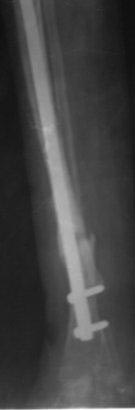

Уважаемые коллеги! помогите советом! Мальчик 2000 г.р. В 2007г получил перелом н/з костей правой голени, в районе лечили гипсом 6 месяцев, сращения нет, в обл.центре КДО аппаратом Илизарова - 3 месяца, после повторная деформация, в НИИТО КДО аппаратом Илизарова -7 месяцев, перелом якобы сросся, но после снятия аппарата через 2 недели после незначительной травмы повторный перелом. И родители начали лечиться у различных табибов и знахарей, мальчик не наступал, ходил с двумя костылями, одели различные ортезы и повязки, и нога сильно атрофировалась.(Мне кажется у ребенка был врожд. ложный сустав, латентная форма) , и в 2011 г, в октябре обратились к нам. , было произведена после рассверливания канала БИОС плечевым стержнем,но стержень пошел по мед.стенке дистального отломка поэтому остался некоторый вальгус(операция без ЭОП) ребенок через неделю начал самостоятельно ходить, клинически деформации нет, все обрадовались, выписали, повторно приехали только ч-з 1,5 года вот с такой деформацией, но ребенок ходит в школу, бегает, незначительно хромает, родители требуют исправить деформацию. Пока в голове один план: удалить стержень, закрытая остеоклазия, аппарат Илизарова из двух колец постепенная коррекция деформации, рассверливание к/м канала, БИОС плечевым стержнем (чуть длиннее), дистально по латеральному кортексу с использованием поллерных винтов и спиц. С уважением Абдурашид.